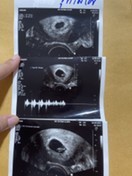

รูปที่1 5w รูปที่ 2-3 6w3d ค่ะ เราไปฝากตั้งแต่ 4w แต่หมอซาวด์ยังไม่เจอน้อง เลยรับฝากตอน 6w3d เจอน้องพร้อมหัวใจเต้นค่ะ

ซาวด์ตอน 5w6d ค่ะ โรงพยาบาลรัฐ เจอน้องแต่ยังไม่เห็นการเต้นหัวใจ หมอบอกน้องยังเล็กอยู่ นัดอีกที เดือน ธ.ค. เลยค่ะ

รูปน้องตอน7สัปดาห์1วันค่ะ ได้ยินเสียงหัวใจแล้ว ตอนนี้น้อง16สัปดาห์แล้ว ท้องแรกเหมือนกันค่ะตื่นเต้นมาก

ของเราซาวด์ตอน5วีค3วัน หมอรับฝากท้องเเต่ยังไม่ได้ยินเสียงหัวใจเด็กคะ ยังเล็กเกินไปหมอนัดอีกที2พย.จ้า